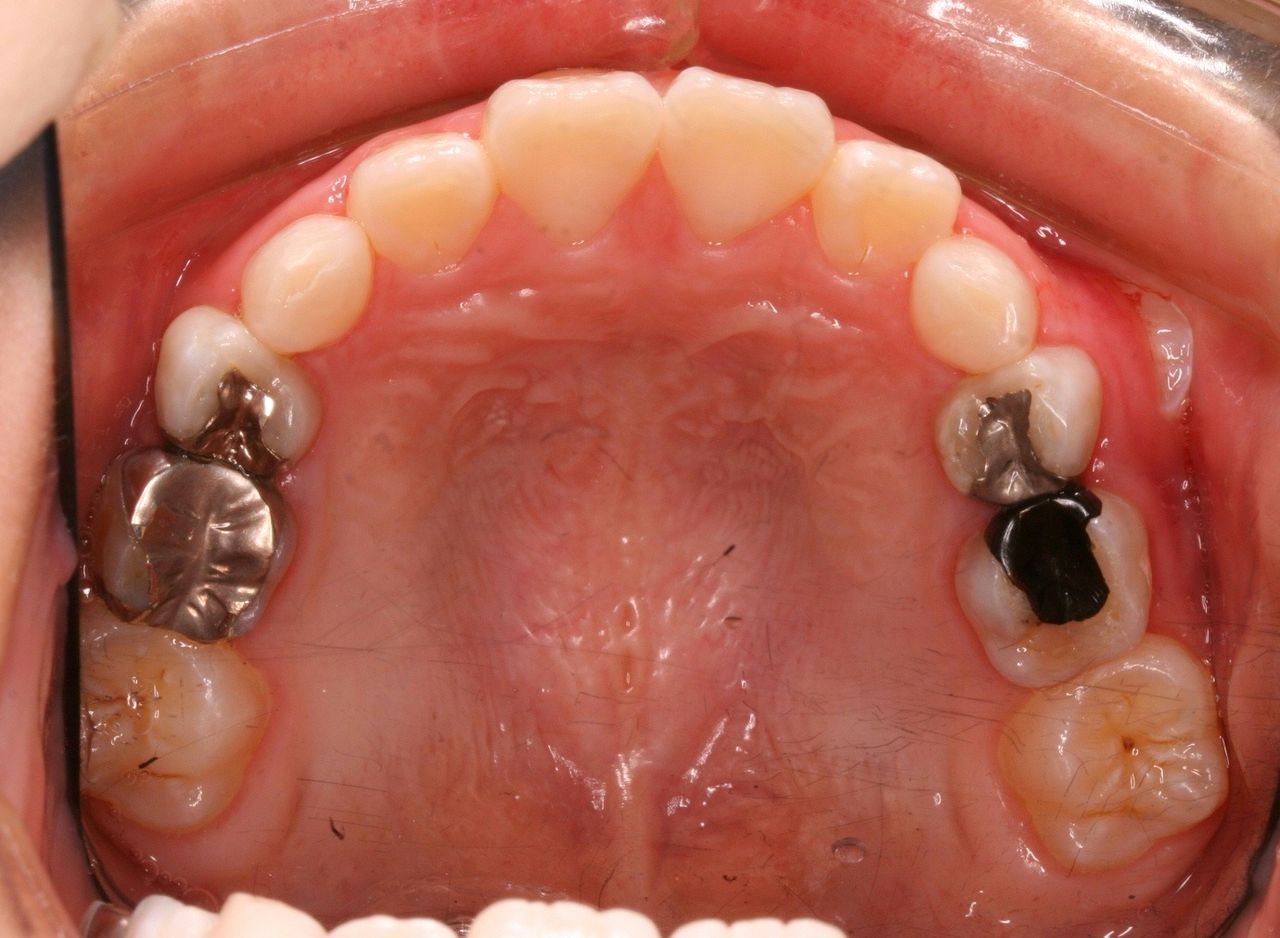

初診時はひどい状況でした。

まず、歯列矯正治療以前に虫歯の管理がまったくされておりませんでした。

年齢は7歳 小学校2年生ですので、 本来なら上下前歯が大人の歯に生えそろい、横の部分は乳歯がすべてある状況です。 いわゆる生えかわりの安定期という時期ですが、この患者さんはすでに何本か乳歯を抜いてしまっております。

また、下の前歯の歯肉も下がってきており、グループ的には1に属するものの、この悲惨は口腔内環境下では、矯正治療をおこなっても散々な結果になることが予想されました。

そこで、徹底したブラッシング練習をおこない、虫歯の治療に関しては近所の歯科医院でお願いしました。

経過をみていくと、変な部分から大人の歯が生えてきました。

乳歯列時期に重篤な虫歯になった場合、あとから生えてくる永久歯は変な場所から生えてくることが多々あります。

理由は、乳歯が虫歯菌によって感染している状況下において、その上にある永久歯の卵はそのままの状況では自分も感染してしまいます。 まれに感染してしまった大人の歯は色が黒ずんだり、形がいびつな奇形的な歯になってしまいます。 多くの場合は感染した乳歯から離れていくのです。 つまり、永久歯の卵は避難しているわけです。